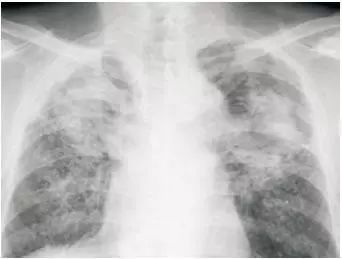

粉尘沉积的肺部X光造影,网络配图